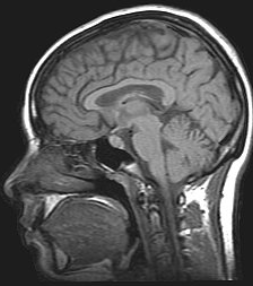

Functional magnetic resonance imaging (fMRI) has intriguing implications for the study of memory in humans, however it can also be used in animal models. fMRI can be used to assess brain functionality in monkeys in the context of a variety of behavioral tasks.[26] Structural MRI can be used to examine the extent and location of brain lesions, so that behavioral abnormalities observed can be directly linked to specific brain structures.[27] High-resolution fMRI can help locate and assess the functionality of large neural networks so that these regions can be further studied using more traditional electrophysiological recording devices.[26]